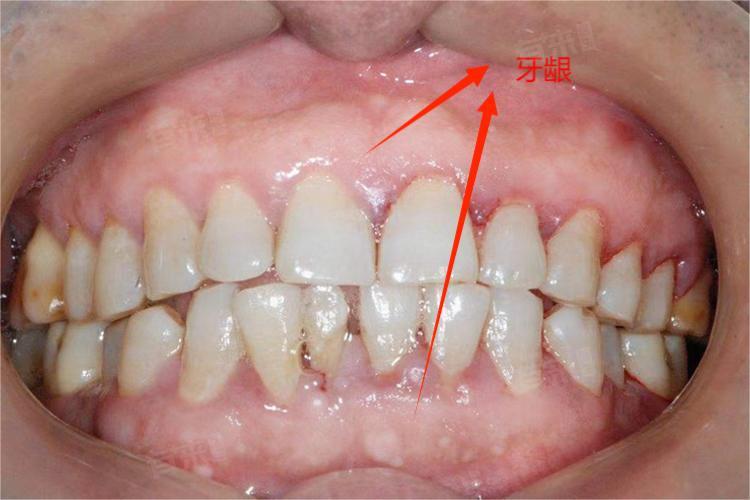

牙龈周围发白可能由多种原因引起,包括缺乏营养、口腔黏膜炎、口腔溃疡、牙槽骨增生、慢性牙周炎、白色角化病、口腔白斑病、贫血等。出现此症状时,建议及时就医进行专业检查和治疗,并保持良好的口腔卫生习惯和定期进行口腔检查。

- 慢性牙周炎:慢性牙周炎是由于长期存在的牙菌斑生物膜引起的牙周支持组织慢性炎症。如果不及时治疗,可能会导致牙龈退缩、牙槽骨吸收等问题,进而影响到牙齿周围的血液循环,使牙龈变薄并失去正常的血红色泽,呈现白色。定期进行牙周清洁和深度刮治以及遵医嘱服用药物可以控制病情。